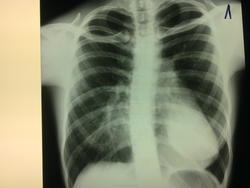

А, что смущает? Смещение сердца? При её комплекции, возможно и норма, или слегка развёрнута (грудинные концы ключиц не симметричные)

сложилась с тенью сердца - получилась такая картина;) а что тень сердца расширена таки напишите!

У нее что, еще и впалая грудная клетка?

Плоская грудная клетка, молочная железа наслоилась на тень сердца. Боковая проекция - что то сильно развернута